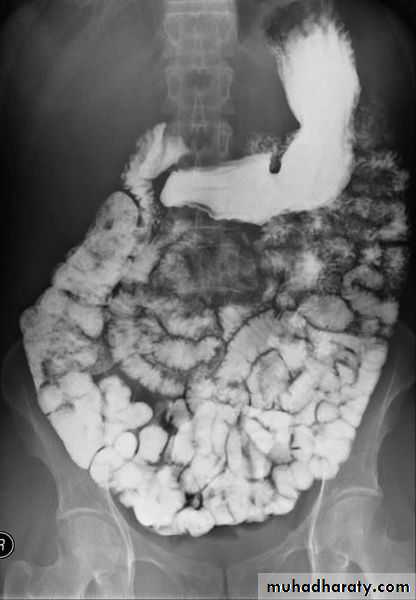

A barium follow-through procedure is a type of medical imaging technique. It is used to evaluate the presence of disease in a person's small intestine.Examination

Barium follow through x-rayThe patient drinks a contrast medium containing barium sulfate. This contrast medium appears white on x-rays, and shows the outline of the internal lining of the bowel. X-ray images are taken as the contrast moves through the intestine, commonly at 0 minutes, 20 minutes, 40 minutes and 90 minutes. This enables the radiologist to assess the bowel as it becomes visible. The test is completed when the Barium is visualised in the terminal ileum and Caecum, which marks the beginning of the large bowel. This is one of the most common places for pathology of the bowel to be found, therefore imaging of this structure is crucial. The test length varies from patient to patient as bowel motility is highly variable.

Radiological appearance of Mal absorption syndrome

* Loss of normal feathery appearance of the small bowel

* Flocculation & segmentation of the Ba

* Widening of the spaces between bowel loops due to mucosal edema

*+/_ spiky appearance of the small bowel loops